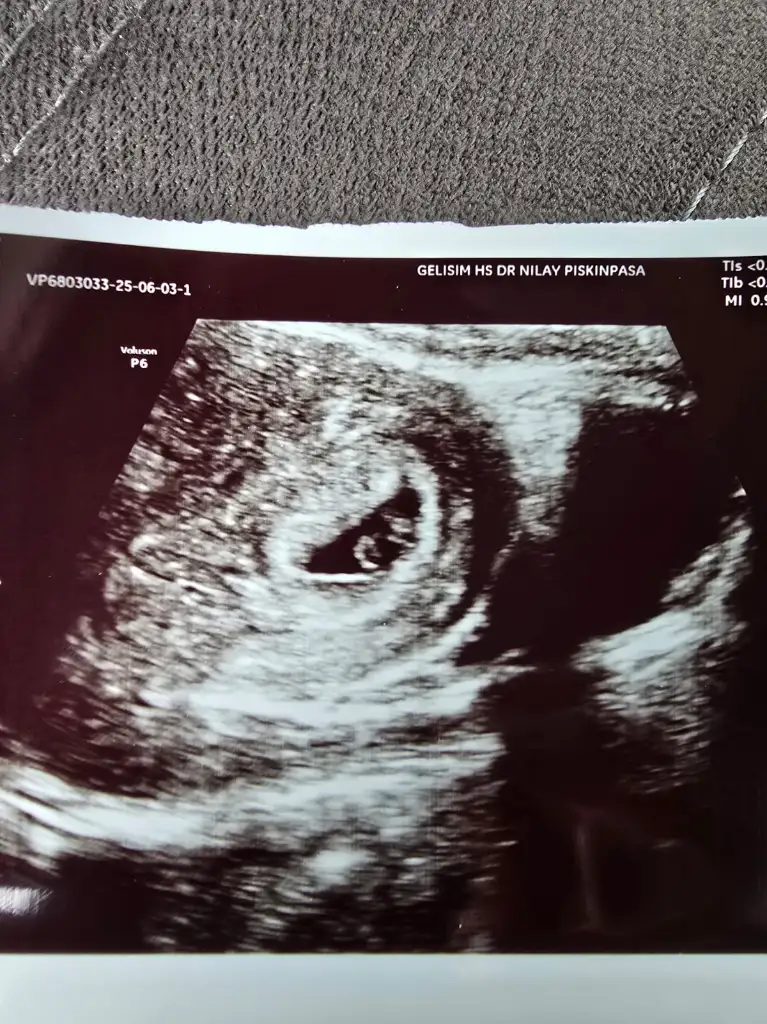

ErkekKızlar 6 haftalık ultrason görüntüsü. Ultrasın görüntüsünden cinsiyet tahmini yapanlar varmış. Bi bakabilir misiniz rica etsem

Erkek gibi geldi bana kesin olmamakla beraber. Sağlıkla gelsin inşallahKızlar 6 haftalık ultrason görüntüsü. Ultrasın görüntüsünden cinsiyet tahmini yapanlar varmış. Bi bakabilir misiniz rica etsem

Ben kese şekli fasulye gibiyse erkek yuvarlaksa kız diye okudumNeye bakıyorsunuz tam olarak ben anlamıyorum da